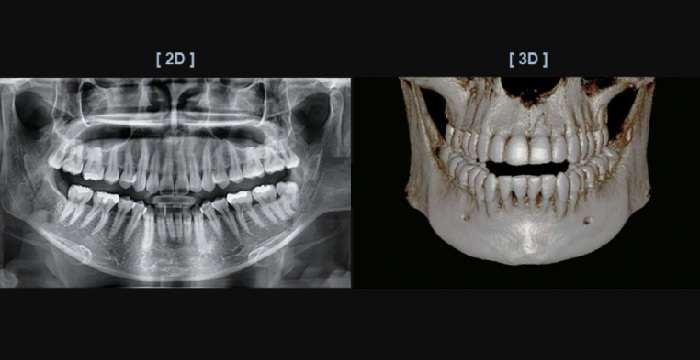

Метод компьютерной томографии позволяет делать повторяющиеся двумерные изображения, которые склеиваются с помощью компьютера для получения трехмерного 3D изображения. 3d снимок зубов сделать довольно просто. Спецканер делает множество рентгеновских лучей под разными углами одновременно.

То есть компьютерная томография это вид рентгеновского снимка, который делает детальные снимки частей тела. Получив такое изображение врачу легче оценить проблему и спланировать лечение. Поэтому если сравнивать обычный рентгеновский 2D снимок и 3D изображение, первый явно проигрывает, так как не показывает всю картину.